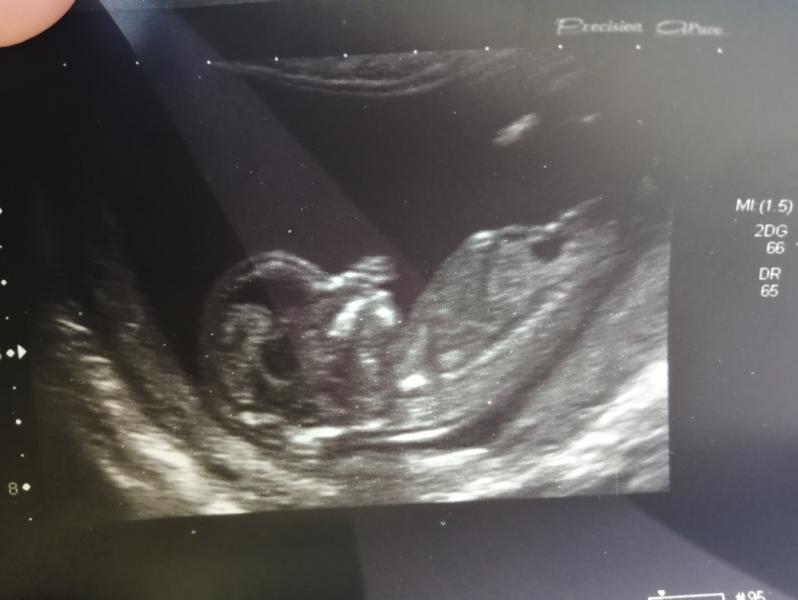

Кто умеет определять пол по УЗИ? Давайте попробуем) на фото срок 13,2 нед. 🤰

Тут ребёнок боком никак не определить , если чисто на уровне экстрасенсорных навыков 🤷🏻♀️😅

Просто сбоку вы так ничего не поймёте

Это нужно снизу как бы смотреть, чтоб точно увидеть что там между ножек 😂